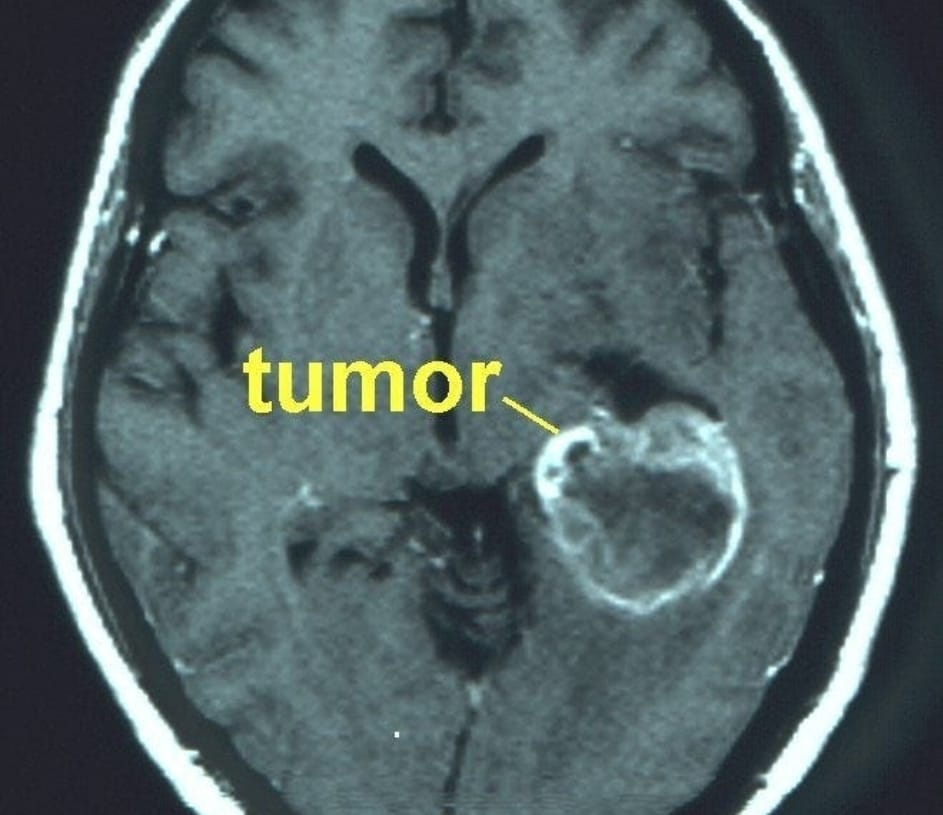

Um estudo pré-clínico inovador publicado na ACS Biomaterials Science & Engineering revelou que a ivermectina nanoformulada administrada por via intranasal reduziu o tamanho do tumor de glioblastoma em 70% — em uma dose menor do que a dose antiparasitária humana aprovada — tudo isso sem nenhum traço de toxicidade no cérebro, sangue ou pulmões.

Tamanho do tumor reduzido em 70%.

· O tamanho médio dos tumores de controle foi de 254 mm³

· Os tumores IVM-NC tiveram uma média de apenas 79 mm³ – uma redução de 70% no tamanho , confirmada pela histopatologia

Esta é a primeira evidência in vivo de que a ivermectina, quando formulada e administrada corretamente, pode suprimir drasticamente o crescimento do glioblastoma em doses muito abaixo dos níveis antiparasitários padrão.

Ao atingir múltiplas características do câncer simultaneamente — proliferação, metabolismo, invasão e sobrevivência — a ivermectina parece atuar como um agente antitumoral multialvo. No glioblastoma, esses efeitos convergentes explicam a redução de 70% no volume tumoral observada com a nanoivermectina intranasal , alcançada em doses abaixo dos níveis antiparasitários padrão e sem toxicidade.

Os resultados demonstram uma redução tumoral de 70% com ausência de toxicidade sistêmica , algo raro em terapias experimentais contra glioblastoma. Essa abordagem nariz-cérebro é especialmente relevante, pois oferece biodisponibilidade cerebral direta, reduzindo os riscos associados à administração sistêmica.